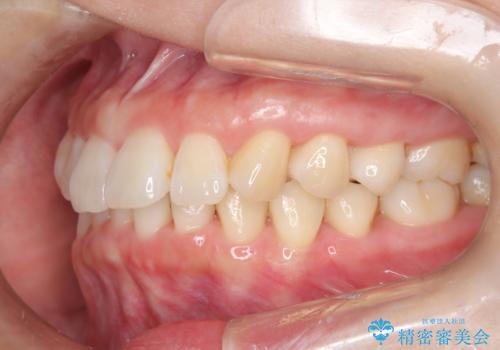

インビザライン ライトパッケージによる部分矯正治療 下の前歯のみの歯並び改善

- インビザライン ライトパッケージパーシャル(下顎のみ)

- 下の前歯の歯並びのみの改善をご希望されました。

インビザライン ライトパッケージ下顎のみ(1枚~14枚まで)での治療を行なっていきました。

マウスピース枚数 初回14枚 + 追加13枚

概ね7ヶ月で治療完了しました。

インビザラインのライトパッケージでは14枚までという枚数制限がありますが、限られた枚数の中で当院独自の工夫を随所に盛り込み、狙い通りの治療結果が得られました。